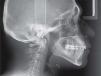

Extraoral examination revealed a proper facial balance and profile, a wide smile and the final orthopantomography, an acceptable root parallelism (Figures 6 to 10).